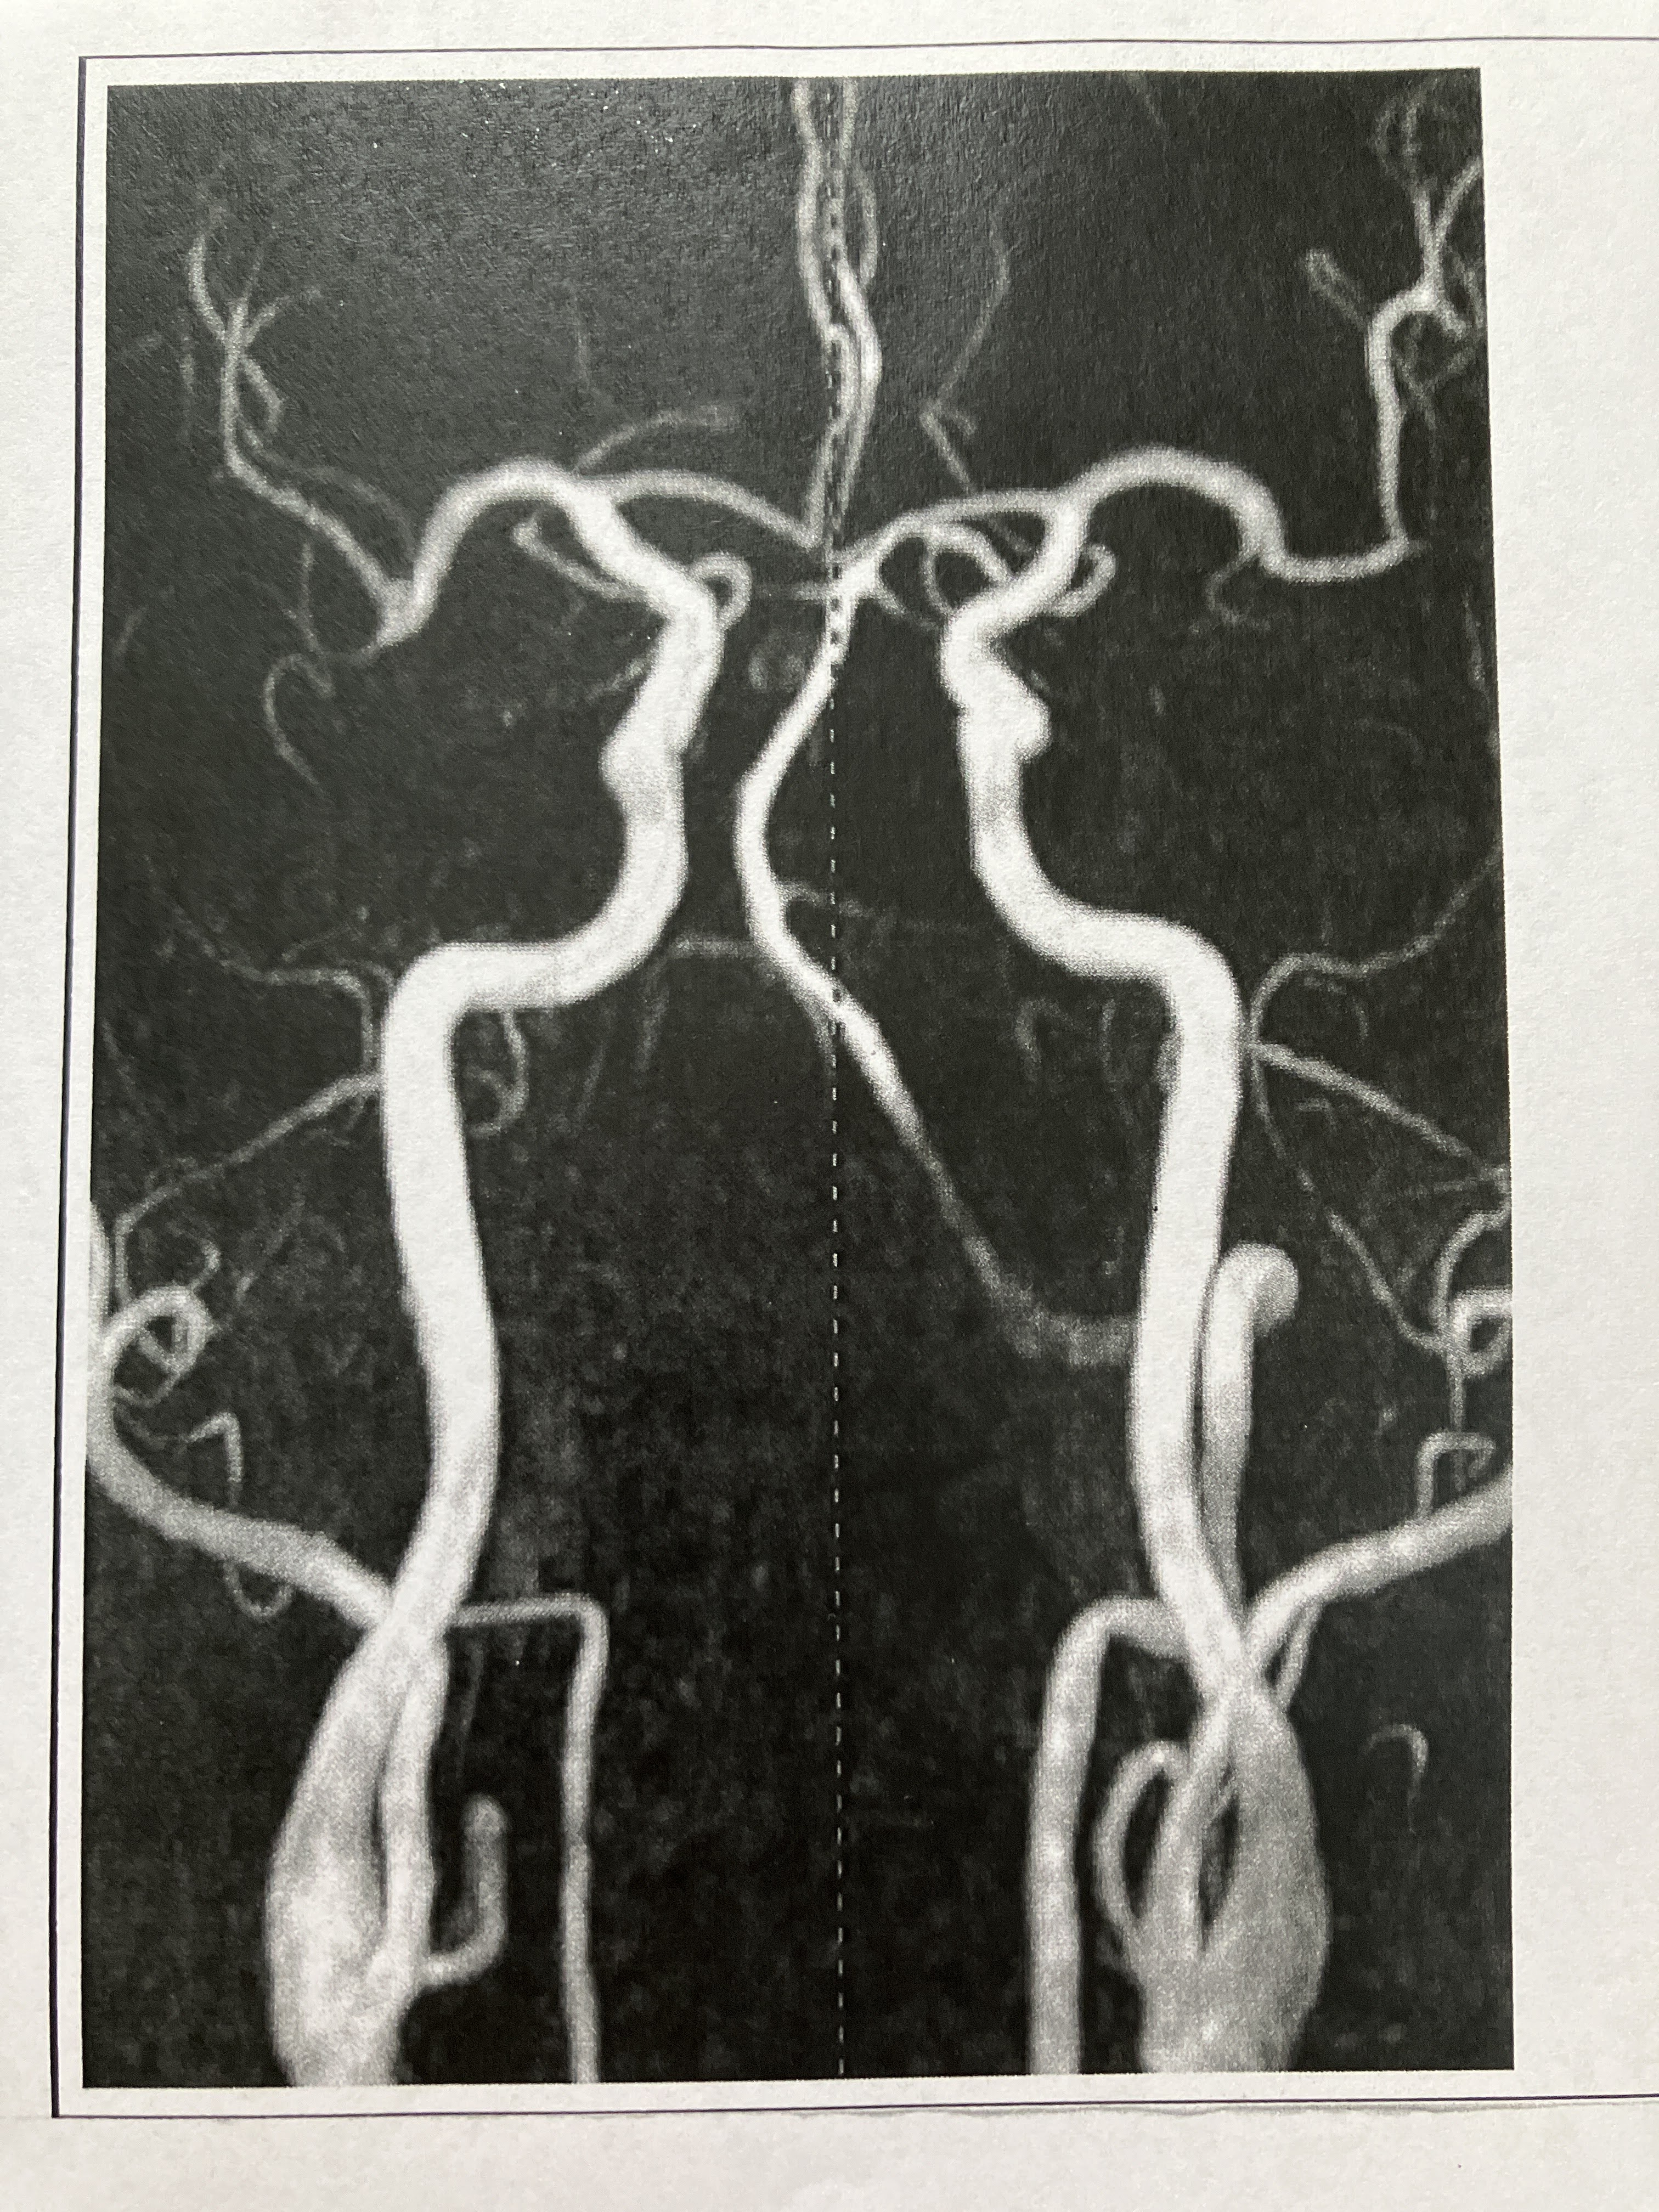

脳ドック

2024.18.14 荒尾市民病院 2023.08.10 荒尾市民病院

22.9.16 荒尾市民病院

2014(H26)7.29 岡山淳風会